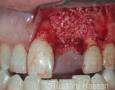

Surgery

2 Months